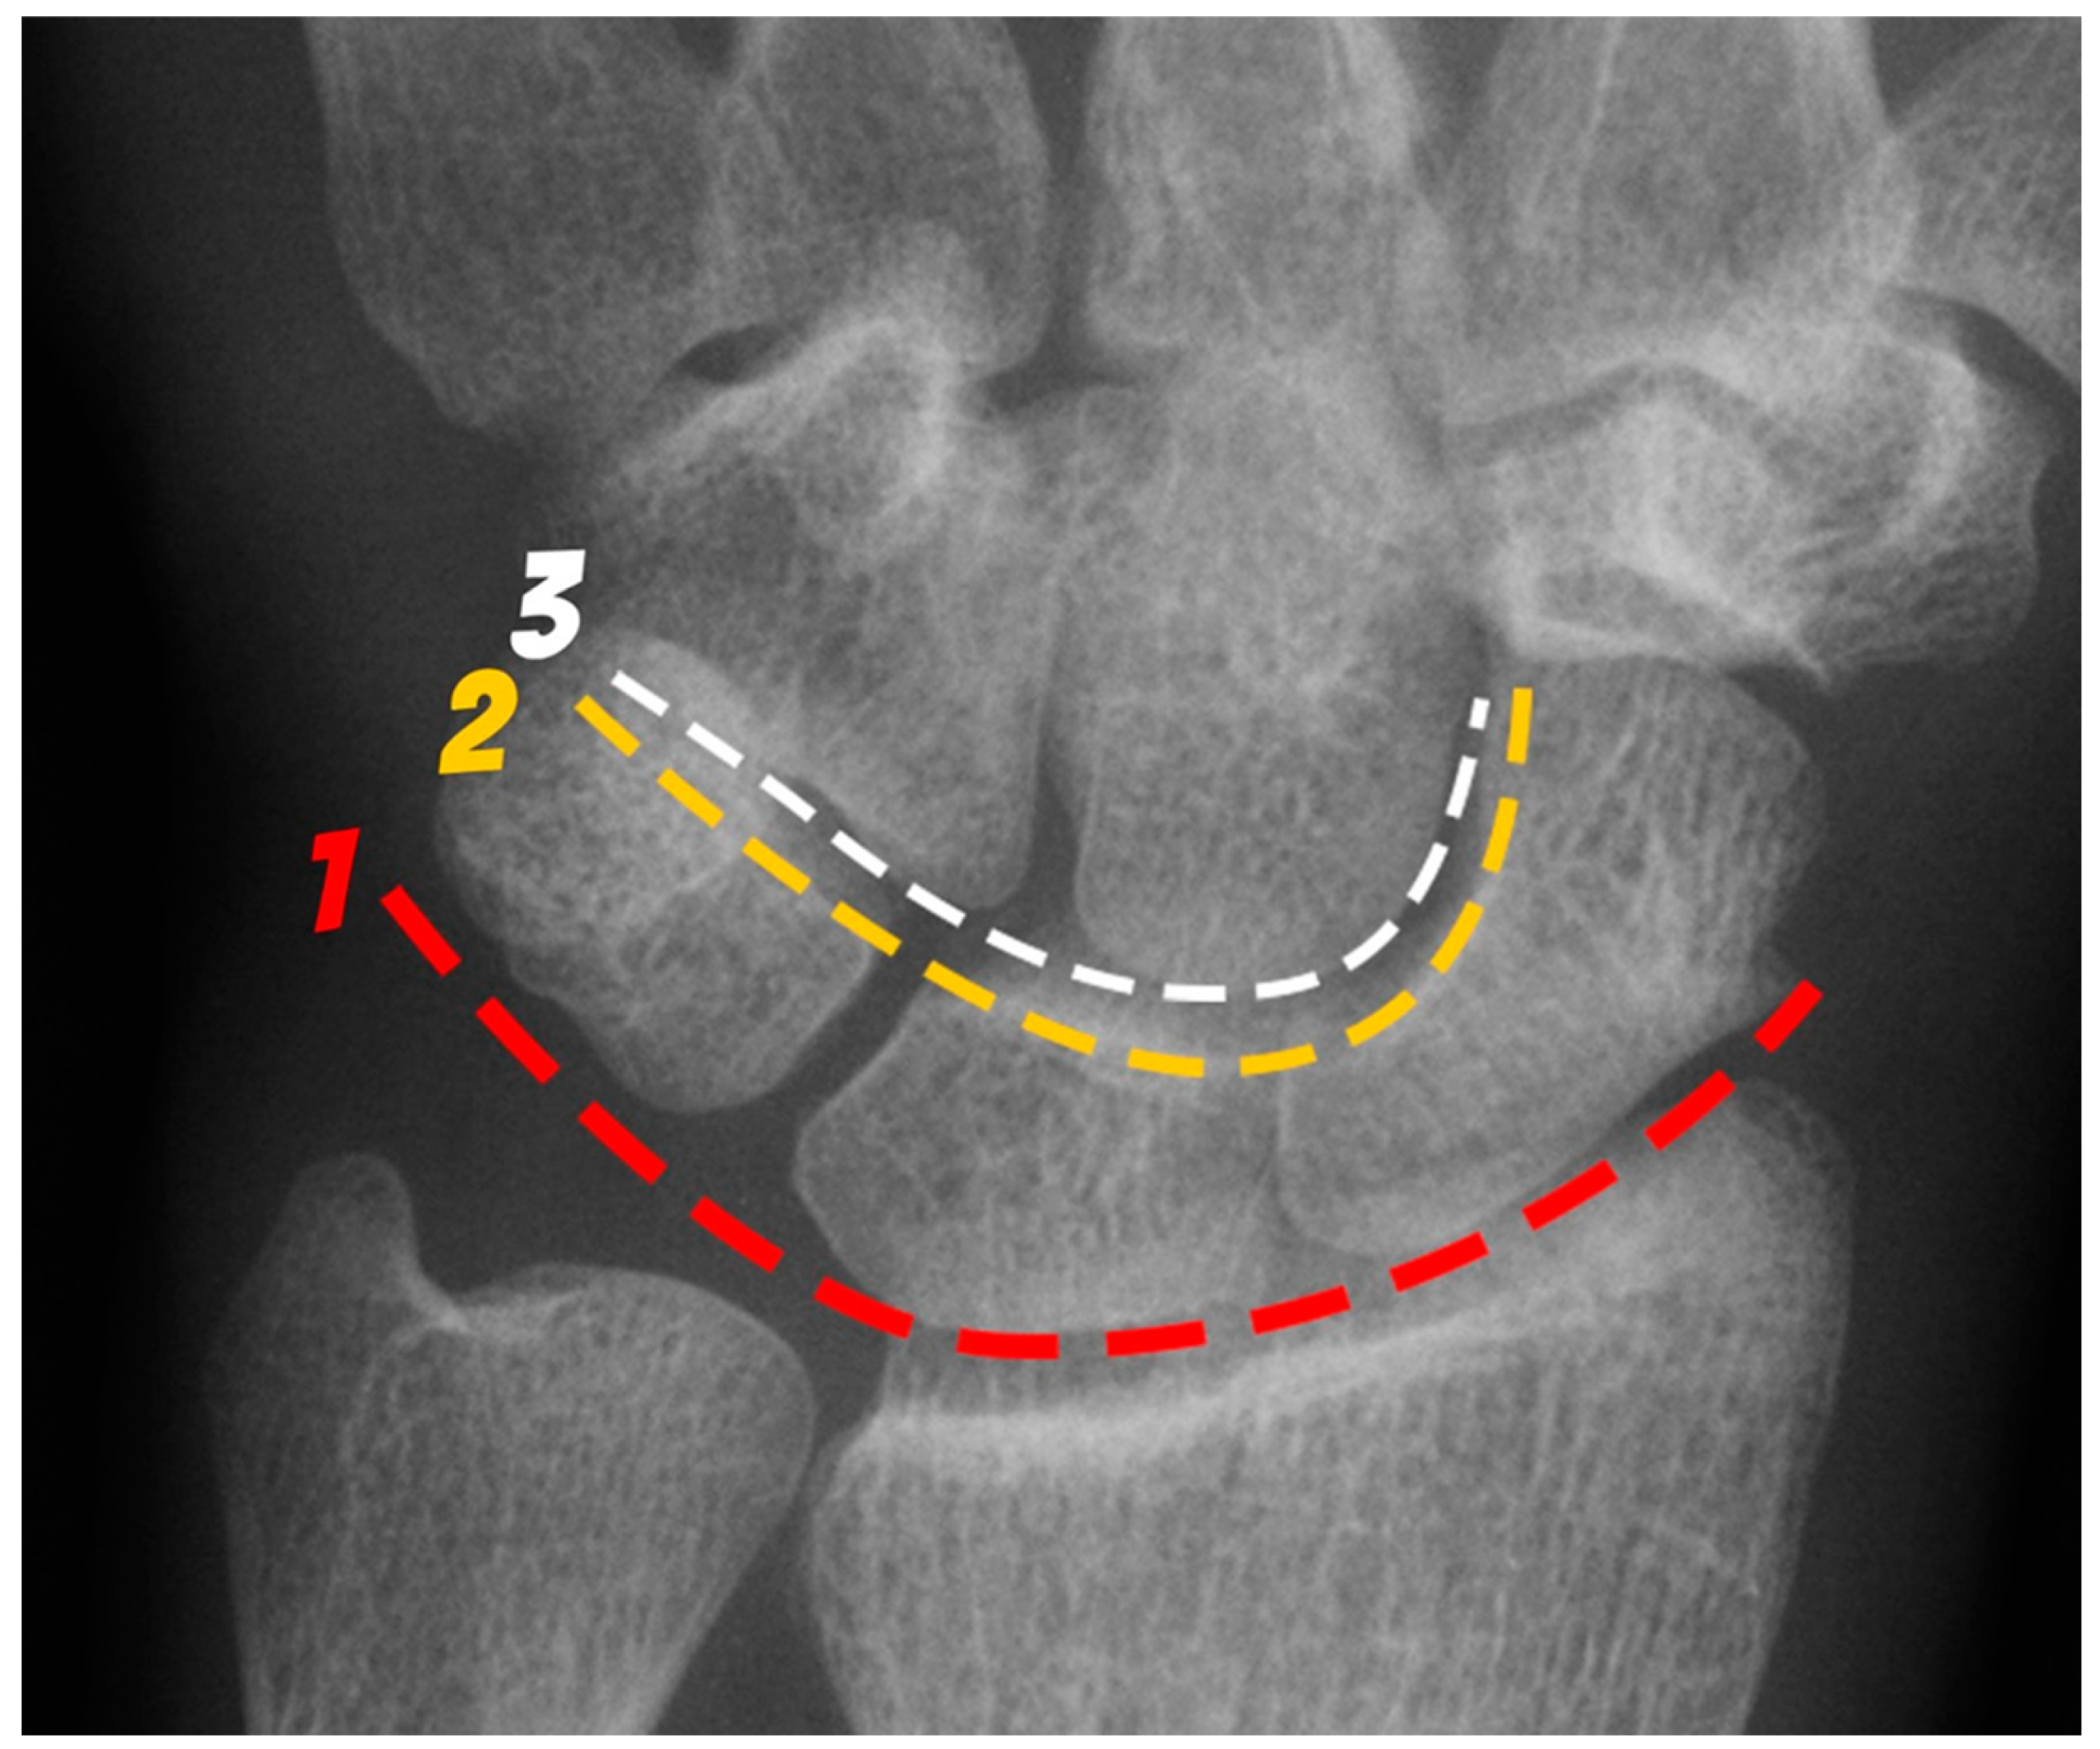

The wrist includes the distal ends of the radius and ulna, the 8 carpal bones, and proximal bases of the metacarpal bones [4]. The carpal bones are divided into a proximal row and distal row. The proximal row, consisting of the scaphoid, lunate, triquetrum, and pisiform bones, is considered an intercalated segment between the radius and distal carpal row. The proximal row is central to maintaining wrist stability by balancing movement and regulating the forces sent to and from the hand and the forearm. The distal row consists of the hamate, capitate, trapezoid, and trapezium bones, which form a more stable and rigid alignment than the proximal row as they function to support the bases of the metacarpals [5]. The arcs of Gilula are used on PA wrist radiographs as part of assessing the normal alignment of the carpus (Figure 1). There are three arcs:

• Proximal (first) arc – smooth line along the proximal surfaces of the scaphoid, lunate, and triquetrum.

• Middle (second) arc – smooth line along the distal surface of the scaphoid, lunate, and triquetrum.

• Distal (third) arc – smooth line along the proximal surface of the capitate and hamate, closely paralleling the second arc.

In a biomechanically normal wrist, there should be no irregularities in the contour of these arcs when traced. Any step-offs/disruptions in these lines suggest a ligamentous injury or fracture at the site of the broken arc [6]. Exceptions include two normal variants, one where the triquetrum is shorter than the lunate creating a step-off of the first arc but normal second arc, and a second when a type II lunate can cause a bilobed appearance of the second and third arcs between the capitate and hamate [7].

Figure 1. PA radiograph of the wrist depicting the arcs of Gilula. The 1st arc (red) outlines the proximal surfaces and the 2nd arc (yellow) the distal surfaces of the scaphoid, lunate and triquetrum. The 3rd arc (white) outlines the proximal surfaces of the capitate and hamate.